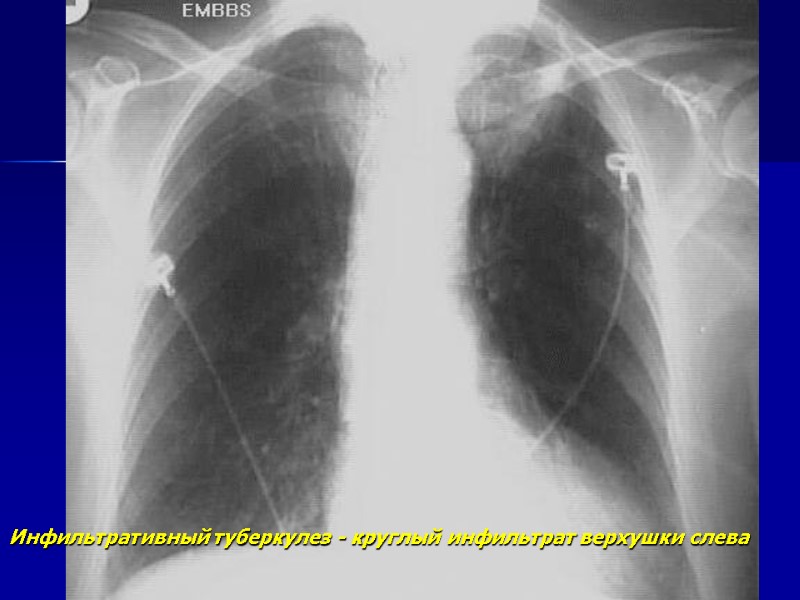

Инфильтративный туберкулез - круглый инфильтрат верхушки слева

Инфильтрат в\доли левого легкого.